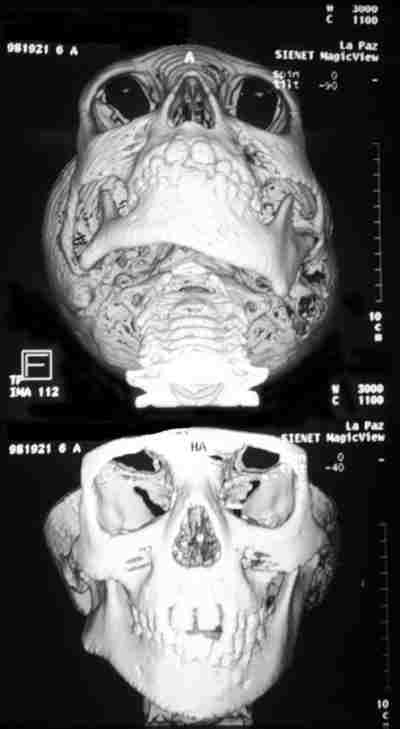

25-02.jpg (14688 bytes)

Figura 2. Reconstrucción tridimensional craneofacial para una mejor valoración de asimetrías.